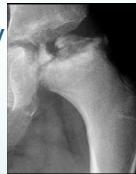

Clinical examination findings:

(Source: Apley’s System of Orthopedics and Fractures)

Physical examination demonstration: